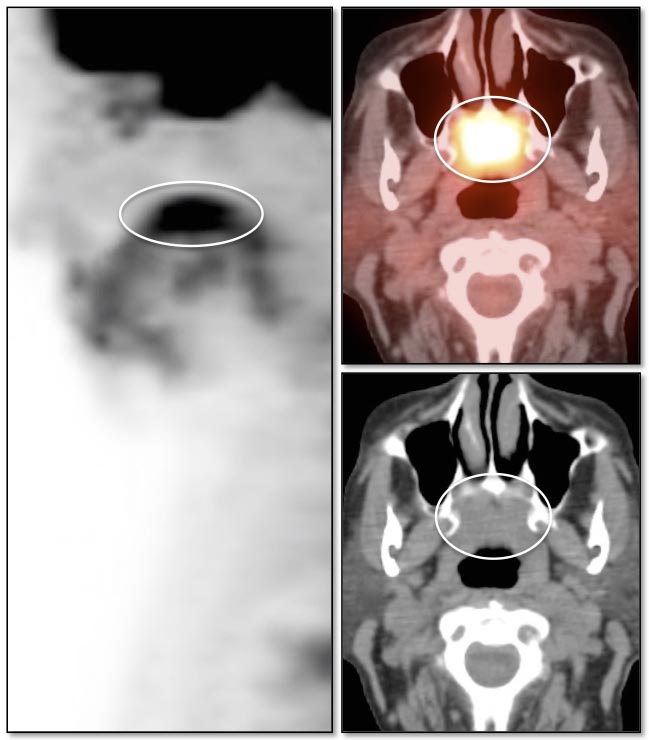

While PET/CT is sensitive for detecting most cancers, there are some malignancies which sometimes demonstrate poor avidity for 18F-FDG, including: [Fig. 1]

- Adenocarcinoma-in-situ (formerly “bronchoalveolar carcinoma”)

Please note that while the above cancers sometimes demonstrate poor metabolic activity, they can also be quite FDG-avid. [Fig. 2]